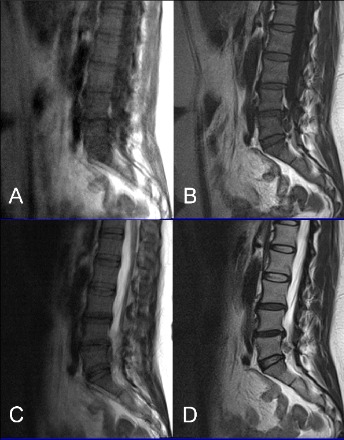

Comparison of T1 FLAIR BLADE with and without parallel imaging against T1 turbo spin echo in the MR imaging of lumbar spine in the sagittal plane

Spinal cord and nerves are best visualized by MRI, which is able to show structural and functional anomalies of the spine. The primary objective of this study is to identify advantages or disadvantages of the T1-weighted fluid attenuated inversion recovery (FLAIR) sequence with BLADE technique (T1W-FLAIR BLADE), with and without parallel imaging when compared with T1 Turbo Spin Echo (T1 TSE) sequence when performing MRI examination of the lumbar spine in a sagittal view. L-spine examinations with T1W-FLAIR BLADE (with and without parallel imaging) and T1 TSE were acquired on 44 patients using a 1.5T scanner. These sequences were assessed by two radiologists a) quantitatively by comparing the signal-to-noise ratio (SNR), contrast-to-noise ratio (CNR) and relative contrast (ReCon) measurements and b) qualitatively based on different features of the images such as cerebrospinal fluid (CSF) nulling.